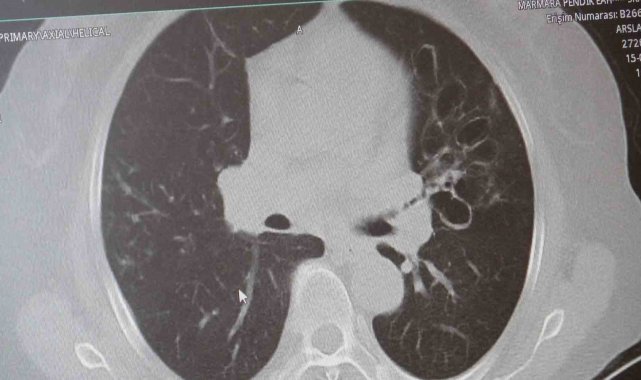

"KOAH toplumda sık görülen bir hastalıktır ve yaklaşık toplumda bunu yüzde 10 civarında görüyoruz. KOAH, zararlı maddelerin akciğeri parçalamasıyla oluşan bir rahatsızlık ve bunun da en önemli nedeni sigara. Vakaların aşağı yukarı yüzde 85'i sigara kullanımından kaynaklıdır. Bunun dışında hava kirliliği, iş yerlerinde kimyasal maddelere maruz kalma ve enfeksiyonlar da yine KOAH'ın nedenleri arasındadır. KOAH'ın önemi şu; bugün Dünya Sağlık Örgütü'nün (DSÖ) dünyada insanları öldüren hastalıklar listesinde ilk 10'da 4'üncü sırada yer alıyor. KOAH önlenebilir bir rahatsızlıktır; sigaranın bırakılmasıyla birlikte tamamen ortadan kalkacaktır."

KOAH'ın akciğer dokusunu tahrip eden bir hastalık olduğunu ve bu nedenle de hastaların enfeksiyona açık hale geldiğine dikkat çeken Karakurt, "Akciğer dokusunun tahrip olduğu her durumda hastaların enfeksiyona karşı eğilimi artar ve enfeksiyona yakalandıkları zaman bunun geçmesi güç olur. KOAH'lı hastalar zatürre geçirdikleri zaman öksürük ve balgam artışı gibi bir takım belirtiler gelişir. Ayrıca ateşin 38,5 derecenin üstüne çıkması, nefes darlığının artması, titremeyle birlikte ateşin yükselmesi ve bir takım bilinç bozukluğu gibi belirtiler hastanın zatürre olduğunu gösterebilir. Bu nedenle hastaların erkenden doktora başvurmaları önemlidir" şeklinde konuştu.

Hastalarda bronşit ve zatürrenin ayırt edebilmesi için belirtilerin doğru tespit edilmesi gerektiğini vurgulayan Karakurt, "Hem zatürrede hem de bronşitte hastalarda öksürük, balgam ve ateş görülür ama burada ikisini ayırt etmek lazım. Bronşit daha çok hava yollarının yani bronşların iltihaplanmasıdır. Zatürre ise hava yollarının uçlarında bulunan ve karbondioksit değişimini sağlayan alveollerin yani hava keselerinin iltihaplanmasıdır. Bronşitten ölüm pek görülmez ama zatürre tehlikelidir; aşağı yukarı yüzde 10 gibi bir ölüm oranıyla seyreder ve bu ölüm oranı yaş arttıkça artar. Ayrım için ateşin yüksek olup olmamasına ve hastada bilinç bozukluğu, solunum sayısının artması ve morarma gibi belirtiler görüldüğü takdirde zatürre olabileceğini düşündürür. Bu gibi durumlarda en kısa zamanda bir sağlık kuruluşuna başvurmak gereklidir" ifadelerini kullandı.